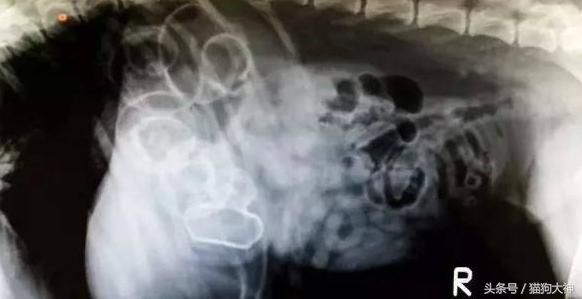

这是一只12岁柯基的胃,由于患上的异食癖,吃了一堆家里盆栽里的土和小石子,把胃都塞满了。这不是一天两天造成的,吃下一堆不能消化的东西狗狗一般会食欲不振,没有精神或排泄困难等表现,如果主人早点关注到,就不会这么严重了。